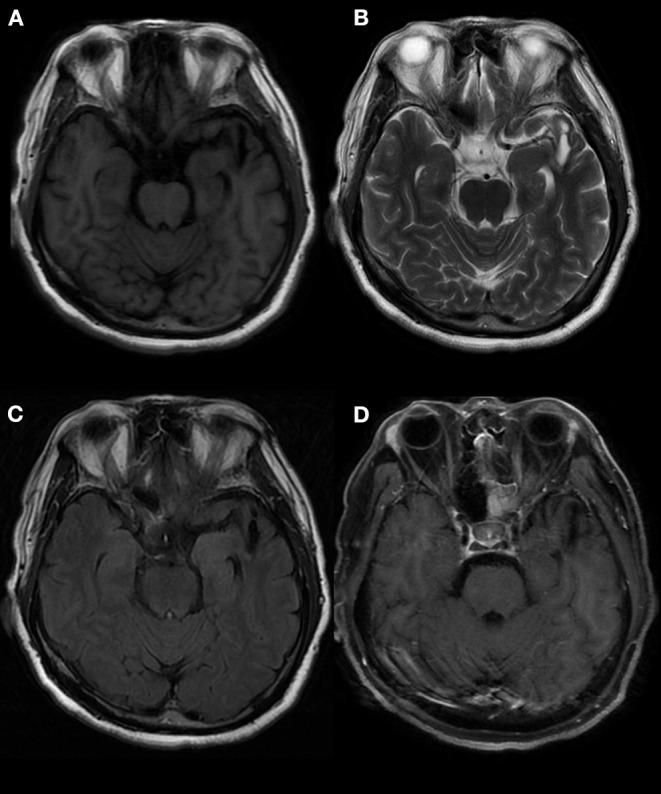

Anti-GABA-B (gamma aminobutyric acid-B) receptor encephalitis is an autoimmune disease mediated by GABA-B-related antibodies. To fully understand the disease, we collected clinical data from patients with GABA-B receptor encephalitis and conducted an analysis to draw conclusions. All patients with GABA-B receptor encephalitis from the Neurology Department of Beijing Tiantan Hospital, affiliated with Capital Medical University, from August 2015 to September 2019 were accepted as study subjects. The clinical data of the patients were analyzed retrospectively and included the general demographic characteristics, clinical manifestations, and auxiliary examinations, including laboratory results, electroencephalograms (EEGs), brain magnetic resonance imaging (MRI), and positron emission tomography (PET-CT) results, as well as treatments. From August 2015 to September 2019, 14 cases of anti-GABA-B receptor encephalitis were diagnosed. Among these patients, middle-aged and elderly men were the main demographic, with an average age of 52 years; moreover, the onset of the disease was relatively sudden, and the time from onset to diagnosis was ~1 month. The main clinical symptoms were frequent epileptic seizures, cognitive dysfunction, and mental behavioral disorders. In seven (50%) patients, the leukocyte in cerebrospinal fluid (CSF) were increased. Five (36%) patients had elevated cerebrospinal fluid protein. In most patients, the oligoclonal bands (83%) of CSF were positive, and 24 h IgG levels (92%) were increased. Anti-Hu or anti-Yo antibodies were positive in two (14%) patients. Tumor markers in 10 (71%) patients indicated that neuron-specific enolase, gastrin-releasing precursor, non-small cell lung cancer-related antigen, or carcinoembryonic antigen levels were increased. EEG results often indicated slow waves, sharp waves, or spike waves in temporal areas. Brain MRI always showed high T2 signals in the medial temporal lobe, hippocampus, and amygdala and swelling in the medial temporal lobe and hippocampus. PET-CT scans almost showed abnormal metabolism in the hippocampus and temporal lobe. Three (21%) patients who underwent systemic PET-CT showed hypermetabolism in pulmonary parenchymal nodules and enlargement of mediastinal lymph nodes. All patients underwent high-dose hormone therapy or immunoglobulin immunotherapy. After treatment, the symptoms of epilepsy, cognitive disorders, and mental behavioral disorders improved to varying degrees. However, one patient died of lung cancer. Anti-GABA-B receptor encephalitis mainly occurred in middle-aged and elderly men, and the disease onset was relatively sudden. Before disease onset, some patients experienced fever and non-specific respiratory symptoms, which mainly manifested as frequent epileptic seizures, cognitive dysfunction, and abnormal mental behavior. MRI and PET-CT revealed abnormal signals and local metabolism, respectively, in the temporal lobe. Moreover, the disease has a close relationship with lung cancer, which requires long-term follow-up observation.

抗GABA - B(γ-氨基丁酸B)受体脑炎是一种由GABA - B相关抗体介导的自身免疫性疾病。为全面了解该疾病,我们收集了GABA - B受体脑炎患者的临床资料并进行分析以得出结论。2015年8月至2019年9月首都医科大学附属北京天坛医院神经内科的所有GABA - B受体脑炎患者均被纳入研究对象。对患者的临床资料进行回顾性分析,包括一般人口统计学特征、临床表现及辅助检查,后者包括实验室检查结果、脑电图(EEG)、脑磁共振成像(MRI)、正电子发射断层扫描(PET - CT)结果以及治疗情况。2015年8月至2019年9月,共诊断出14例抗GABA - B受体脑炎患者。这些患者中,中老年男性为主,平均年龄52岁;疾病起病相对突然,从起病到诊断的时间约为1个月。主要临床症状为频繁癫痫发作、认知功能障碍及精神行为障碍。7例(50%)患者脑脊液(CSF)白细胞增多。5例(36%)患者脑脊液蛋白升高。大多数患者CSF的寡克隆带(83%)呈阳性,24小时IgG水平(92%)升高。2例(14%)患者抗Hu或抗Yo抗体呈阳性。10例(71%)患者的肿瘤标志物显示神经元特异性烯醇化酶、胃泌素释放前体、非小细胞肺癌相关抗原或癌胚抗原水平升高。EEG结果常显示颞叶有慢波、尖波或棘波。脑MRI总是显示内侧颞叶、海马和杏仁核T2信号增高以及内侧颞叶和海马肿胀。PET - CT扫描几乎均显示海马和颞叶代谢异常。3例(21%)接受全身PET - CT检查的患者显示肺实质结节代谢增高及纵隔淋巴结肿大。所有患者均接受了大剂量激素治疗或免疫球蛋白免疫治疗。治疗后,癫痫、认知障碍及精神行为障碍症状均有不同程度改善。然而,1例患者死于肺癌。抗GABA - B受体脑炎主要发生于中老年男性,起病相对突然。发病前部分患者有发热及非特异性呼吸道症状,主要表现为频繁癫痫发作、认知功能障碍及精神行为异常。MRI和PET - CT分别显示颞叶有异常信号及局部代谢异常。此外,该疾病与肺癌关系密切,需要长期随访观察。